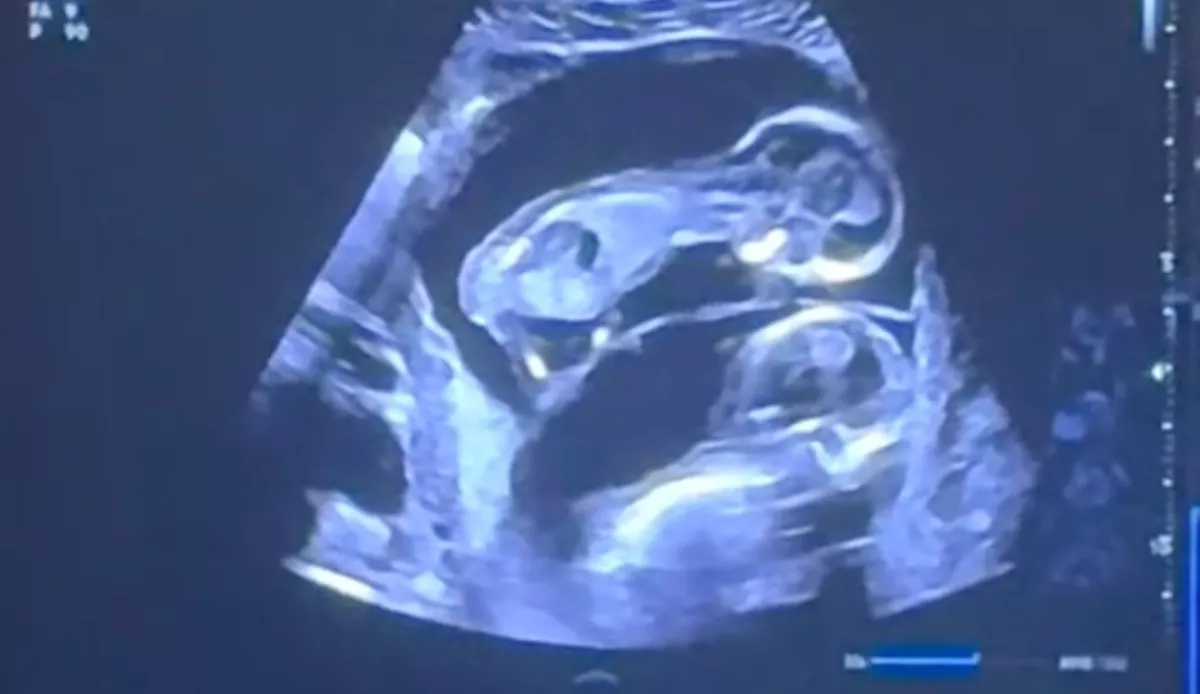

Mivel az amszterdami Michelle de Bruijn az ultrahangos videót az orvos monitoráról le is filmezte, és nemrégiben feltöltötte a TikTokra, most mindenki láthatja. A felvételen úgy tűnik, mintha a felül látható baba néhány puszit adna az alatta lévőnek a fejére. Hogy ez tényleg így volt-e, azt mindenkinek magának kell eldöntenie. A várandós nő számára azonban egyértelmű, hogy igen. Nemrégiben egy interjúban áradozott az élményéről:

„Látni ezt a két kis lényt az anyaméhben, ahogy megtapasztalják egymás iránti szeretetüket, egyszerűen leírhatatlan volt.”